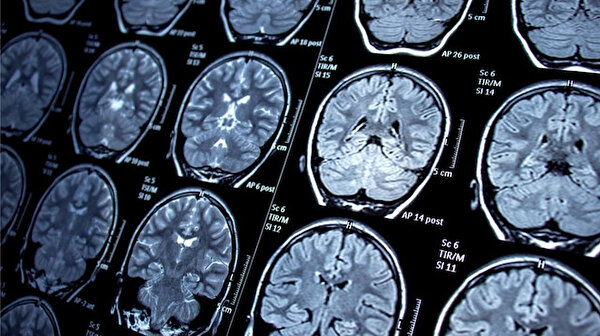

Araştırmacılar, burun yoluyla uygulanan damlaların merkezi sinir sistemine ulaşarak ölümcül beyin kanseri glioblastomaya karşı etkili olabileceğini gösterdi. Farelerde yapılan deneyler, ilacın hedefe güvenli şekilde ulaştığını ve tümör büyümesini önlediğini ortaya koydu. Bu yöntem, geleneksel tedavilere dirençli tümörler için yeni bir umut vadediyor.

Washington Üniversitesi’nden bilim insanları, burun yoluyla verilen damlaların sinirler üzerinden beyne ulaşıp glioblastoma tedavisinde etkili olabileceğini keşfetti. Ön testler, ilacın farelerde güvenli bir şekilde hedefe ulaştığını ve tümörlerin büyümesini durdurduğunu gösterdi. Glioblastoma, agresif yapısı ve erken tespit edilememesi nedeniyle klasik tedavilere direnç gösteriyor.